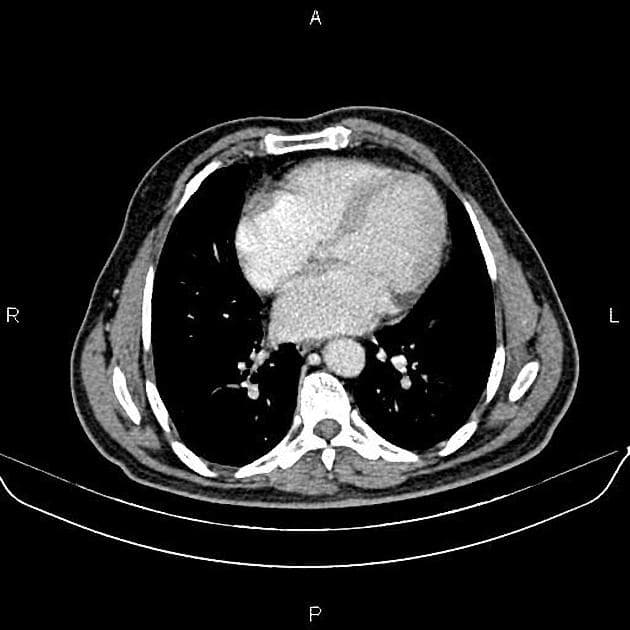

- Tổn thương dạng nốt tại mặt dưới thuỳ gan trái, có tín hiệu đồng tín hiệu so với nhu mô gan, trừ thì động mạch sau khi tiêm thuốc cản quang, khi đó tổn thương cho thấy ngấm thuốc thì động mạch.

- Có sẹo trung tâm nhỏ.

Trường hợp điển hình của tăng sản tuyến foca (focal nodular hyperplasia - FNH).

- "Đặc điểm hình ảnh điển hình bao gồm tổn thương ranh giới rõ, đồng tín hiệu trên hầu hết các chuỗi xạ hình, tăng ngấm mạnh ở thì động mạch và sẹo trung tâm tăng ngấm muộn."

Tăng sản tuyến foca (FNH) là tổn thương gan lành tính phổ biến thứ hai sau u máu, chủ yếu ảnh hưởng đến phụ nữ trẻ đến trung niên. Bệnh được cho là do phản ứng tăng sản tại chỗ trước một dị dạng mạch máu khu trú, thường xảy ra trên nền gan bình thường. Tổn thương thường xuất hiện như một khối ranh giới rõ, không có vỏ bao, với sẹo trung tâm hình sao đặc trưng và tăng ngấm thuốc đồng đều mạnh ở thì động mạch. Trên cộng hưởng từ, FNH cho hình ảnh giảm tín hiệu ở chuỗi T1, tăng tín hiệu ở chuỗi T2 so với nhu mô gan, và đồng tín hiệu ở thì chức năng gan do sự hiện diện của tế bào gan và ống mật nhỏ hoạt động. Sẹo trung tâm tăng ngấm thuốc ở thì muộn. Mặc dù FNH thường không triệu chứng và được phát hiện tình cờ, cần phân biệt với u tuyến tế bào gan và các tổn thương di căn tăng sinh mạch. Sinh thiết hiếm khi cần thiết nếu hình ảnh điển hình. Điều trị chủ yếu là theo dõi bảo tồn, không cần cắt bỏ trừ khi có nghi ngờ chẩn đoán hoặc bệnh nhân có triệu chứng.